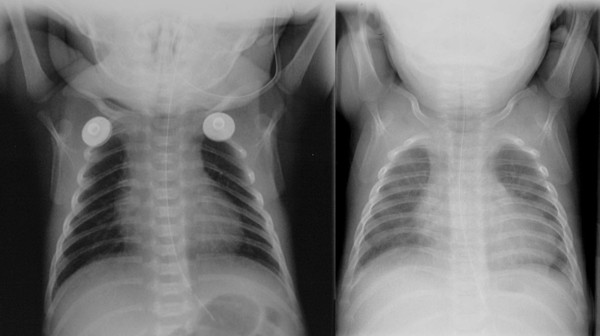

Pedirad